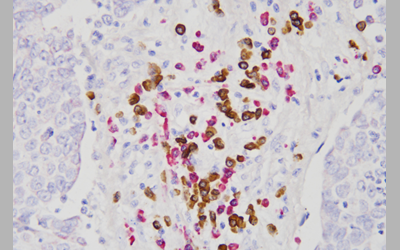

FLC ها در چندین فرآیند کلیدی پاسخ های ایمنی شرکت می کنند. آنها برای تنظیم عملکردهای پلی مورفونوکلئرها ( PMN ) و کمک به پیش تحریک PMN ضروری هستند. علاوه بر این، آنها باعث دگرانولاسیون ماست سل می شوند که واسطه های پیش التهابی را آزاد می کند و پاسخ های التهابی موضعی را در برخی شرایط مانند بیماری التهابی روده (IBD) با داشتن وزن مولکولی کم که ممکن است مستقیماً برای سلول های لوله پروگزیمال (PTCs) سمی باشد، تحریک می کند. FLC ها همچنین می توانند نقش مهمی در بیماری های کلیوی داشته باشند. شواهد محکمی وجود دارد که نشان می دهد ایمونوگلوبولین ها به طور گسترده ای در طول پاسخ های ایمنی میزبان درگیر هستند. ایمونوگلوبولین ها حاوی دو زنجیره سنگین مساوی و دو زنجیره سبک مساوی هستند که از طریق پیوندهای دی سولفیدی به هم متصل شده و ساختارهای تترامری را تشکیل می دهند. در سیستم ایمنی پستانداران، زنجیره های سبک از دو زیرگروه، κ یا λ تشکیل شده اند. همراه با تولید و مونتاژ کل ساختار ایمونوگلوبولین، سلول های B همچنین می توانند زنجیره های L آزاد κ و λ را در سرم انسان، حدود 500 میلی گرم در روز، از نظر فیزیولوژیکی ترشح کنند. در انسان، هر سلول پلاسما تنها یک نوع زنجیره ایجاد می کند. ژن‌های کدکننده زنجیره λ و κ بر روی کروموزوم‌های مختلف (به ترتیب کروموزوم‌های 22 و 2) سازمان‌دهی شده‌اند. در افراد سالم، FLC های پلی کلونال( κ و λ )در مقادیر زیادی تولید می شوند. مشخص است که نئوپلاسم های پلاسما سل فقط زنجیره های سبک κ یا λ ترشح می کنند.

از نظر عملکردی، FLC ها پروتئازهای آنزیمی هستند که می توانند لکوسیت ها را برای تقویت عملکرد آنها تحریک کنند. از سوی دیگر، FLC ها استرس اکسیداتیو را در طیف متنوعی از سلول ها و بافت ها تحریک می کنند و به طور مستقیم به سلول های اپیتلیال کلیه و کاردیومیوسیت ها آسیب می رسانند. FLCها همچنین می توانند پلیمریزه شوند که بر اساس ایزوتیپ متفاوت هستند. در حالی که زنجیره های سبک انباشته شده در آمیلوئیدوز زنجیره های لامبدا هستند، تقریباً تمام بیماری های رسوب زنجیره سبک به دلیل زنجیره های کاپا هستند.